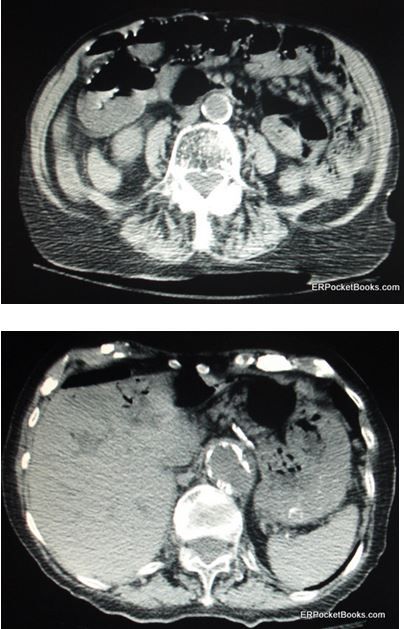

Here: a close-up look at one cause of upper GI bleeds, as well as bezoars, stromal tumor, appendicolith, and Kaposi sarcoma.